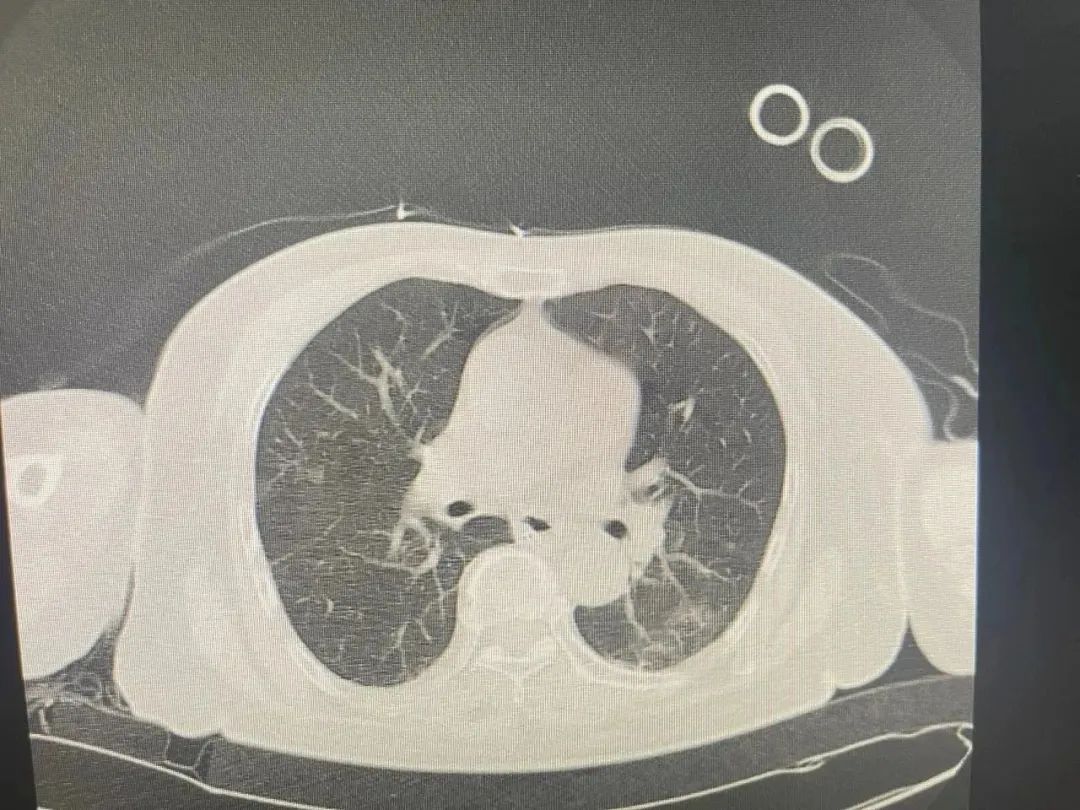

因误吸引发的肺部感染终于爆发

双侧胸腔积液严重

治疗前

治疗后

11号肺部检查明显好转